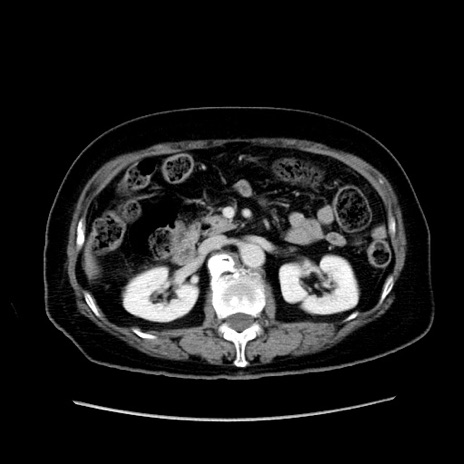

症例19(横断像)

【症例】80歳代女性

【主訴】下腹部痛

【現病歴】約8時間前より下腹部痛の出現あり、救急外来受診。

【既往歴】両側付属器切除

【身体所見】意識清明、下腹部正中に手術痕あり、その部位に一致して圧痛と反跳痛あり。腸蠕動音は亢進。

【データ】WBC 9300、CRP 0.15